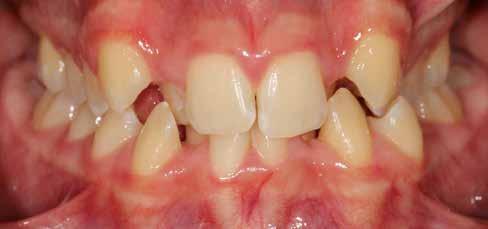

Ebben a cikkben egy 16 éves lánypáciens esetét szeretném bemutatni (1–7. képek)

Mint sok páciensem, akiknél végül nincs szükség állcsontműtétre, ők is megjárták a saját „kálváriájukat”: már több fogszabályozó kollégánál jártak, és mindegyik azt mondta nekik, hogy állcsontműtét nélkül az eset nem megoldható.

Végső elkeseredésükben időpontot foglaltak hozzám, és legnagyobb örömükre egyértelműen látszódott, hogy a Pitts Protokollok-kal nincs szükség az orthognáth műtétes beavatkozásra.